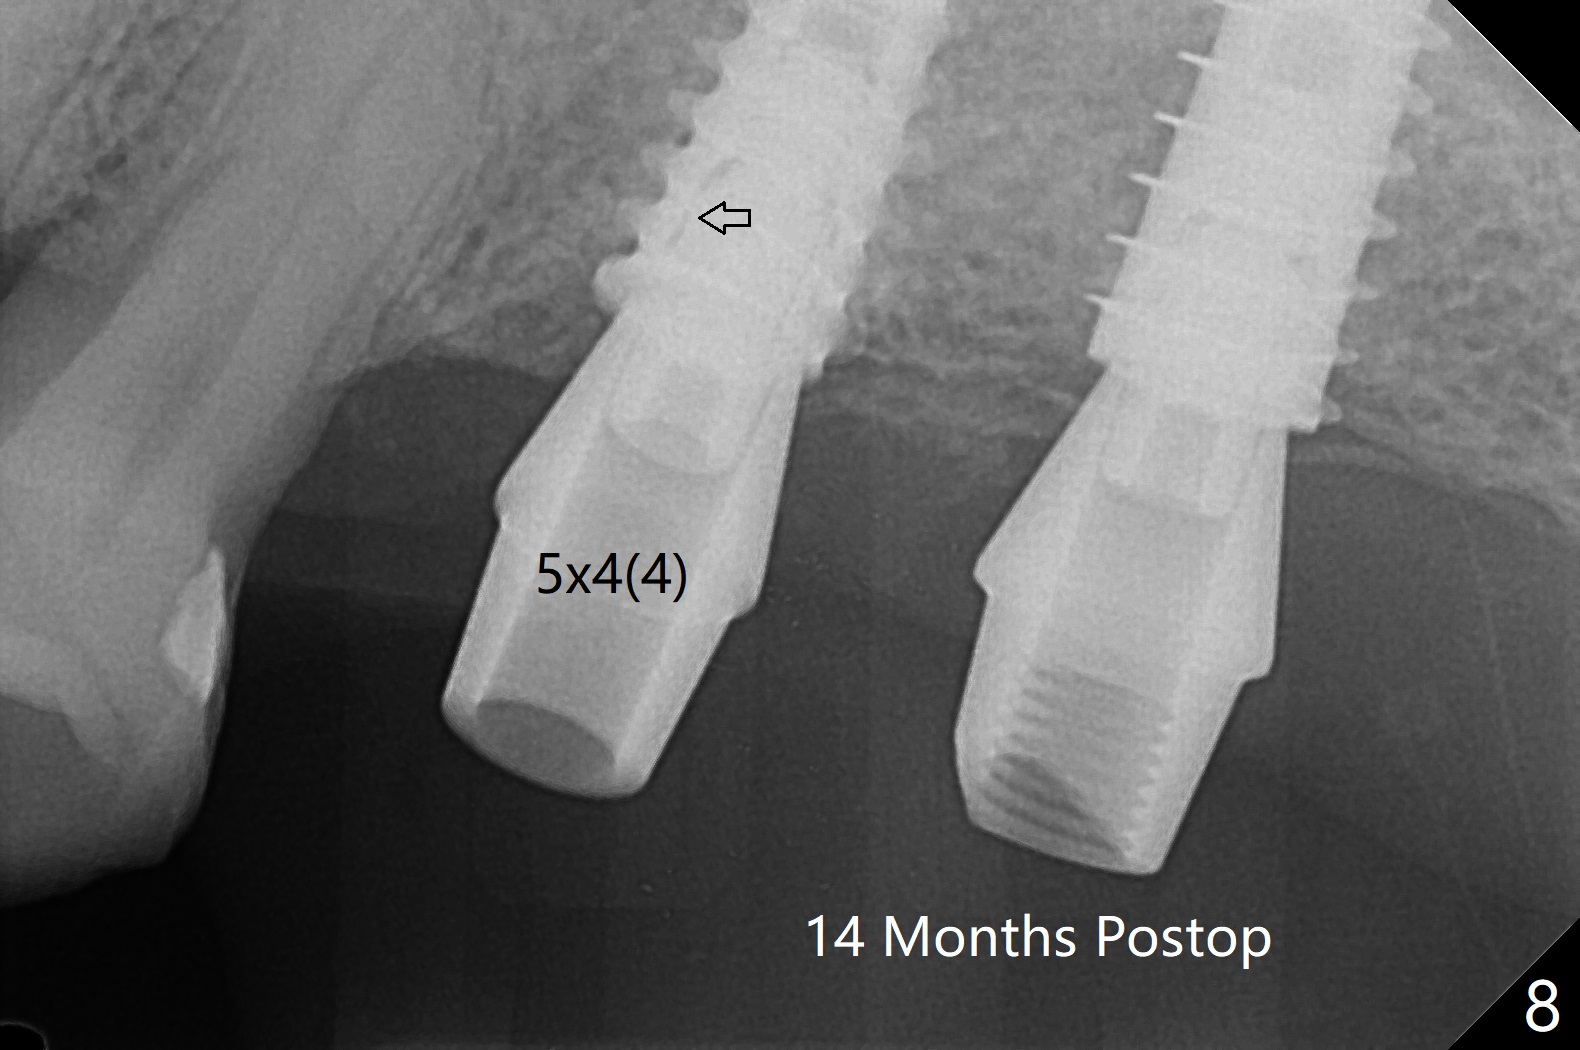

After finishing osteotomy with IS guide and Tatum Tapered tap 5x14 mm for 11 mm (gingival level) free hand, a 5x11 mm Tatum implant is placed at #18 with >15 Ncm (Fig.1). Bone harvested from the site of #18 will be used for #15 sinus lift (Fig.2 * as well as allograft). By the similar fashion, osteotomy at #15 is finished according to IS drill sequence except underdrilling (4.0x7.3 mm drill with 2 O-rings). Following use of DIO Sinus Approach Kit and placement of 2 pieces of PRF membrane and mixture of autogenous and allograft for sinus lift, a 4.5x11 mm IBS dummy implant is placed (Fig.2). With more allograft for sinus lift, a 5x9 mm implant is inserted with >35 Ncm (Fig.3). At #18 the implant 2.5 months postop (Fig.4) seems ok with removal of the cover screw and placement of a healing cuff. The implant at #15 appears osteointegrated with sinus lift 2.5 months postop (Fig.5 *). Half month later, the implant at #18 is tender associated with unipost placement. The healing abutment returns. A pair abutment (5.5x4(4) mm; 25 Ncm) is placed at #15. When the patient returns 7 months postop, BWs are taken to confirm that the abutment at #15 is fully seated, whereas that at #14 is not (Fig.6). A healing abutment is then placed at #14. Osteointegration seems to occur at #18; there is no tenderness when a 4.5x3 mm abutment is placed (Fig.7). Provisional crowns are fabricated at #15 and 18 for progressive loading. When the patient returns 14 months postop, a 5x4(4) mm hex abutment is placed at #14 with apparent gap between the implant and abutment (Fig.8 (PA) open arrow). In fact the gap seems to be absent more coronally as shown by bitewings (Fig.9,10 <). All of the 3 crowns are cemented in situ (Fig.11, 12) although the one at #14 is removed with the abutment for removal of residual cement. When the latter is re-torqued, the abutment remains completely seated (Fig.12). However, the implants at #15 and 18 appear to be placed distally with free-end guides (black lines).